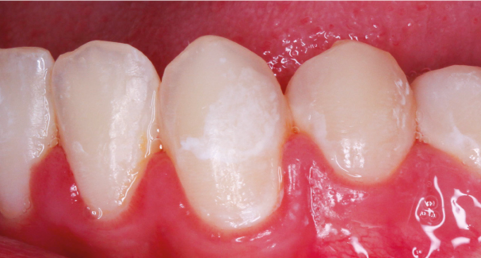

La première phase du cycle correspond à la déminéralisation. Elle se définit comme la fuite de certains éléments minéraux constitutifs (calcium, phosphate) des tissus minéralisés par dissolution acide [7]. Celle-ci provient donc soit de la production d’acides dans le biofilm avec une libération d’ion H+, soit d’une origine intrinsèque ou extrinsèque. Lorsque la solution acide entre en contact avec l’émail, elle diffuse à travers le biofilm. Ce n’est qu’après qu’elle peut interagir directement avec les tissus minéralisés de la dent, et plus précisément avec les cristaux d’hydroxyapatite qui composent l’émail, puis pénétrer dans le gel aqueux qui occupe le réseau des pores de l’émail. Il se produit donc une perturbation des équilibres ioniques au niveau de l’interface tissu dentaire/gel aqueux du biofilm [8].